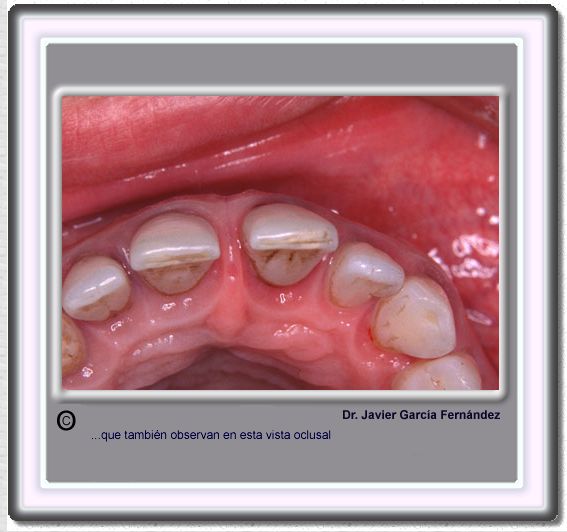

image 633